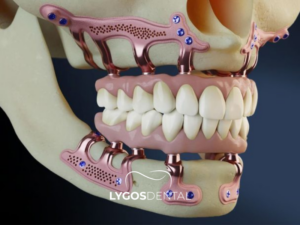

Subperiostal implant, çene kemiğinin üzerine yerleştirilen ve diş protezlerini desteklemek için kullanılan özel bir implant türüdür. Bu implant türü, kemik içine yerleştirilen klasik implantlardan farklıdır. Metal bir çerçeve, çene kemiğinin üst kısmına konumlandırılır.

Diş eti dokusu iyileştikten sonra çerçevenin uçları ağız içinde görünür hale gelir. Bu uçlara sabit diş protezleri yerleştirilir. Genellikle çene kemiği hacmi yetersiz olan hastalarda tercih edilir. Subperiostal implant, kemik içine implant yerleştirmenin zor olduğu durumlarda alternatif bir tedavi seçeneği sunar.

Subperiostal İmplant ile klasik implant arasındaki en temel fark, implantın kemiğe yerleşim biçimidir. Klasik implant sistemlerinde implant, çene kemiğinin içine yerleştirilir ve zaman içinde kemikle bütünleşmesi beklenir. Subperiostal İmplant sisteminde ise taşıyıcı yapı kemiğin içine değil, kemiğin üzerine konumlandırılır ve diş eti altından destek alınır.

Subperiostal İmplant tedavisinde öncelikle çene yapısına uygun özel bir planlama yapılır. Tedavinin mantığı, kemiğin yüzeyine uyum sağlayacak bir taşıyıcı sistemin hazırlanmasına dayanır. Bu yapı, diş eti altına yerleştirilir ve ağız içinde protezi taşıyacak destek noktaları bırakılır. Böylece ileri kemik kaybı bulunan bölgelerde, kemiğin içine yerleştirilen klasik implantlara alternatif bir destek mekanizması oluşturulur. Uygulama sürecinin başarısı, sistemin çene kemiğiyle uyumlu biçimde tasarlanmasına ve yumuşak dokularla dengeli şekilde ilişkilendirilmesine bağlıdır.